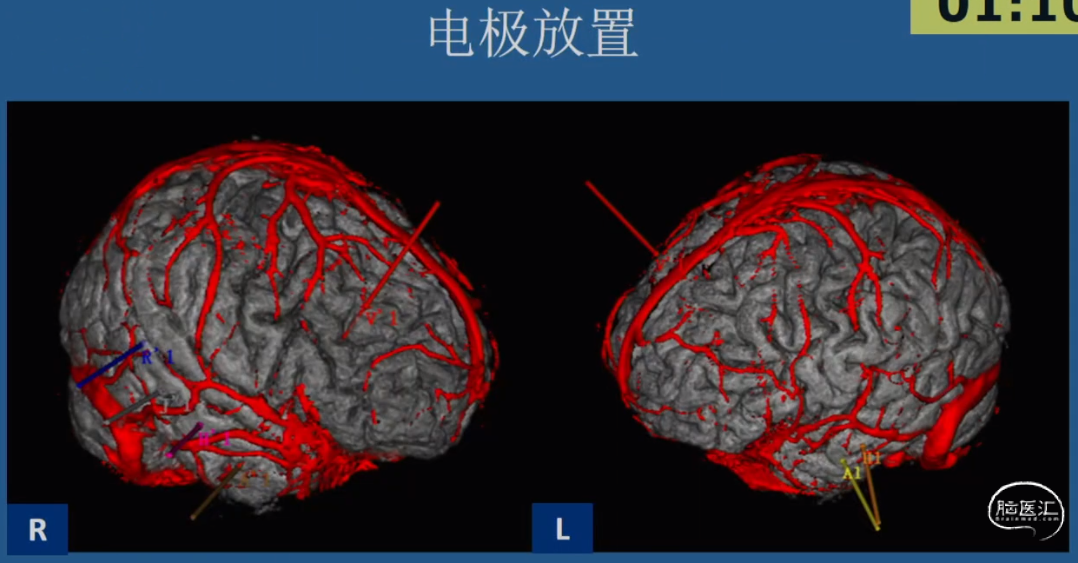

•术前评估非常重要

-脑电(头皮EEG、侵袭性EEG)

-各种影像(MRI、PETCT...)

03.SEEG手术评估